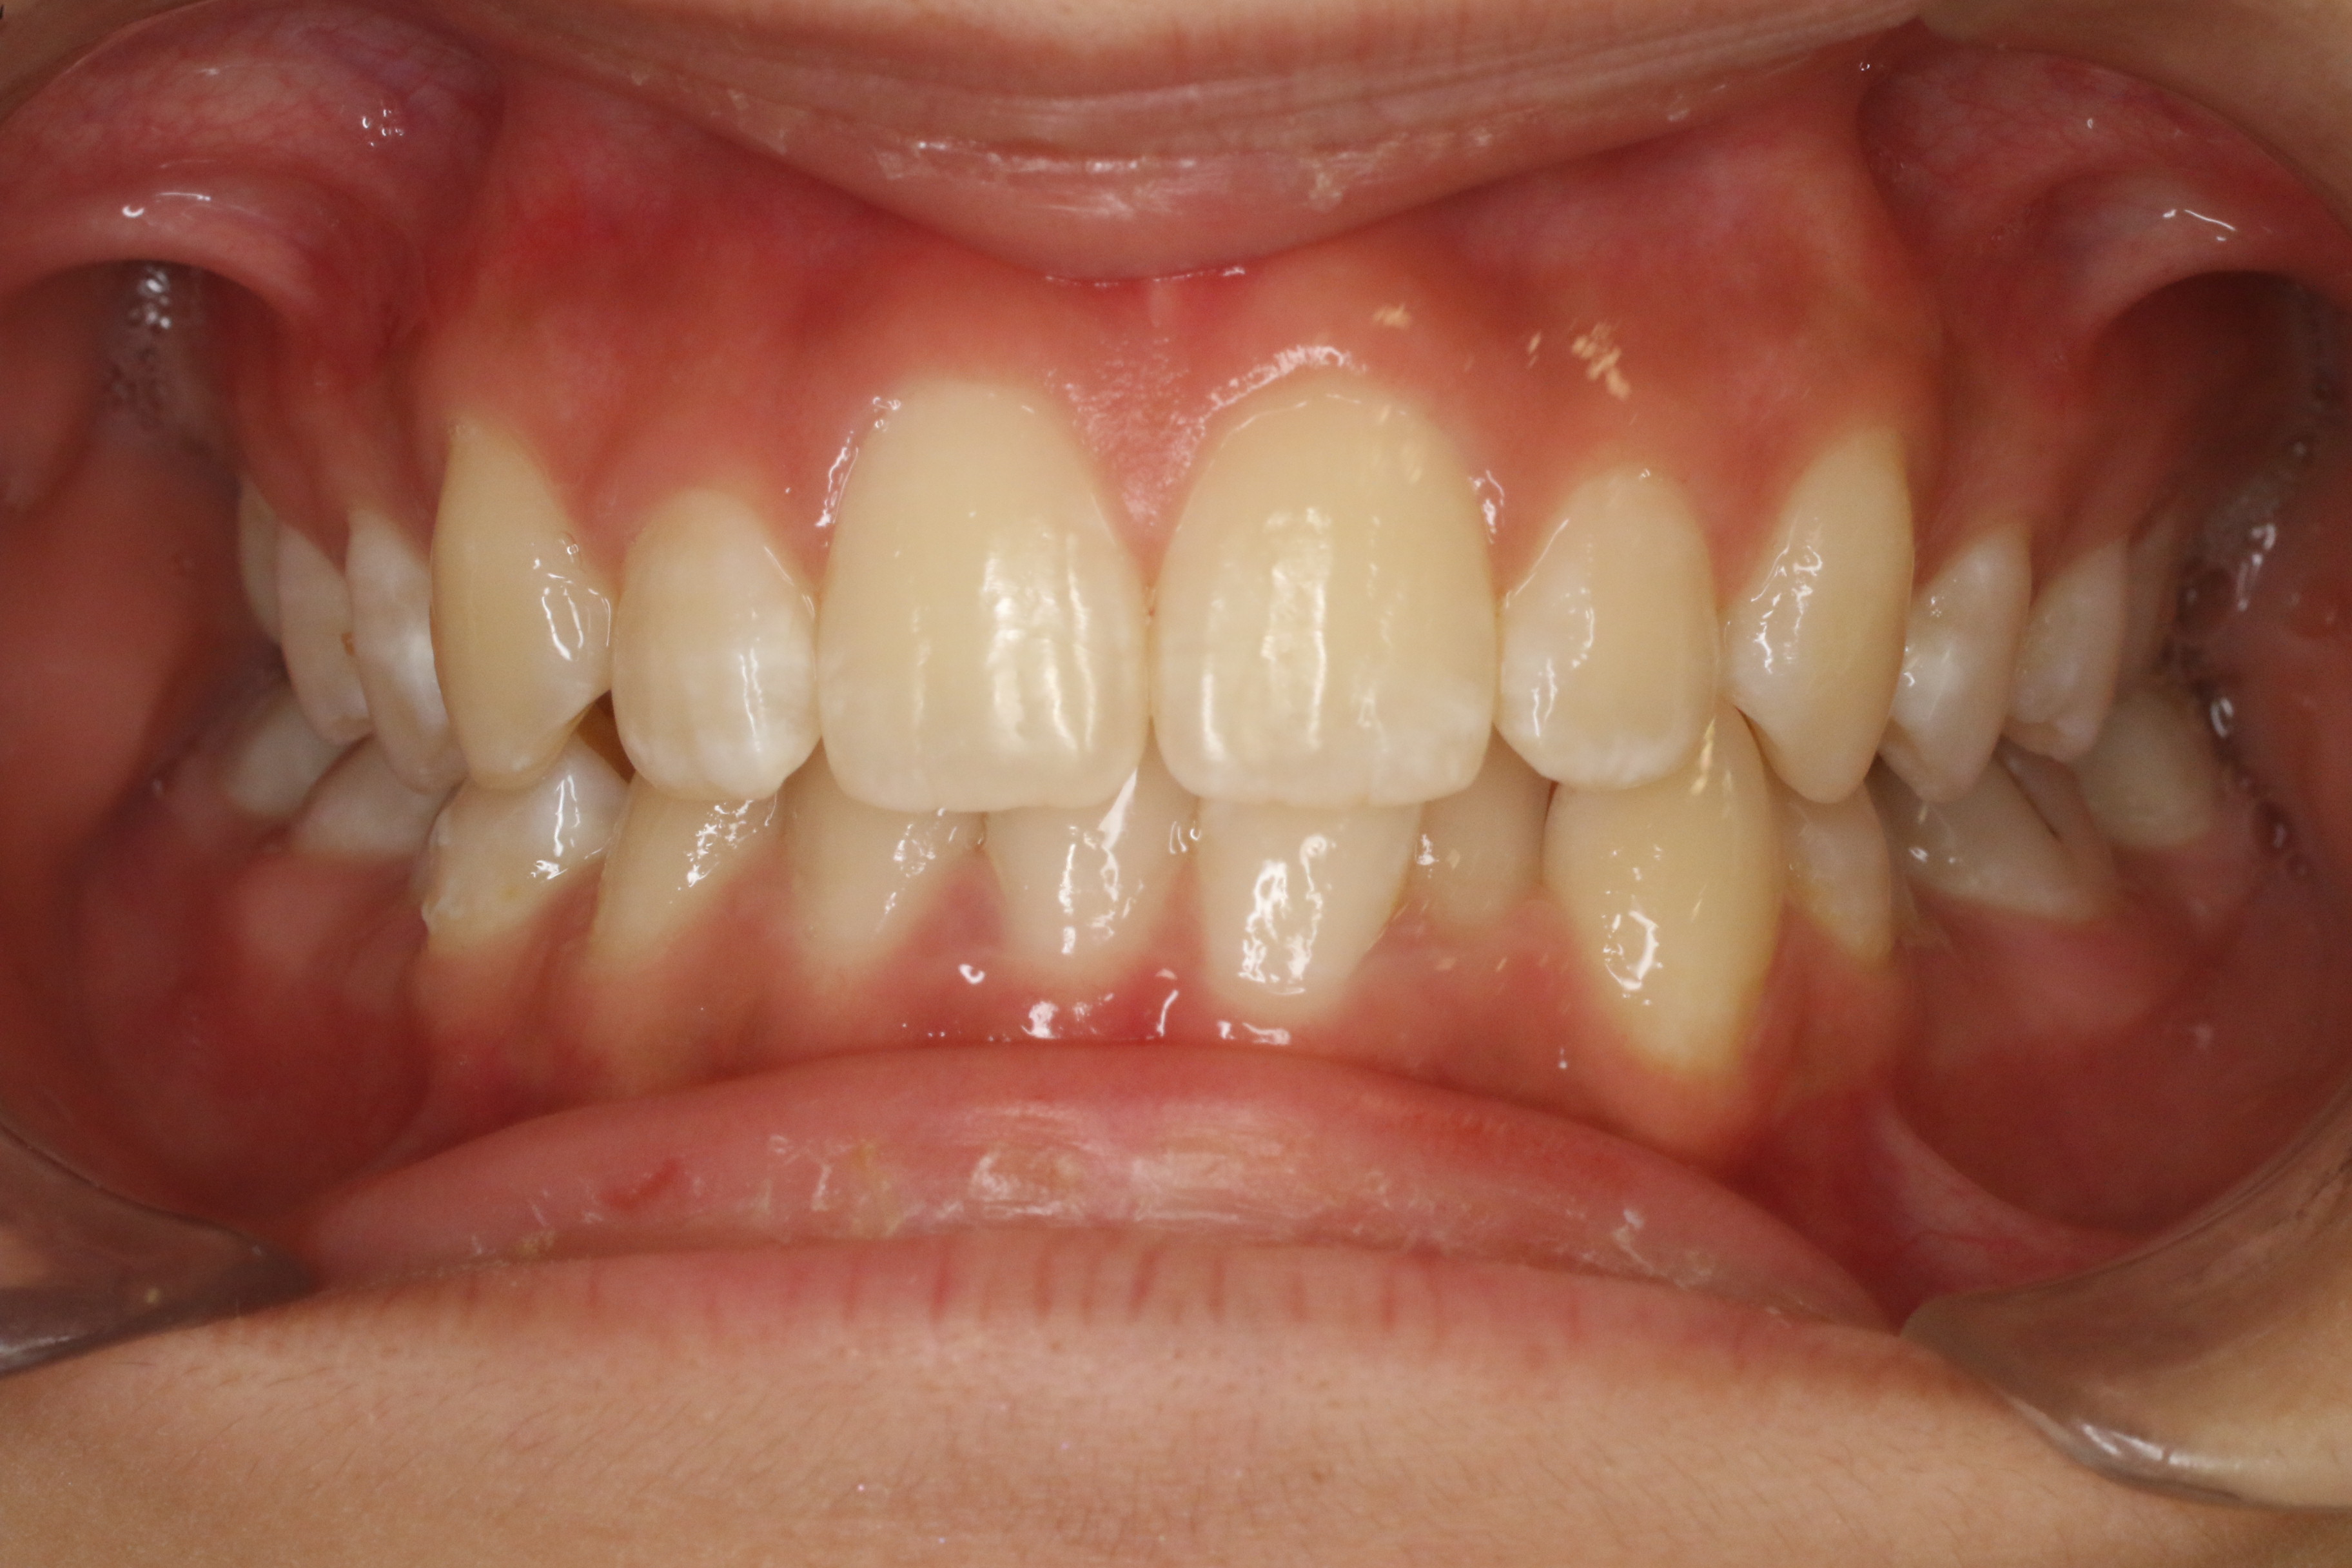

すきっ歯を治したい

年齢層 20代

性別 女性

主訴 【主訴】すきっ歯を治したい 【診断・症状】空隙歯列、1,1正中離開

治療費用 検査・診断:38,500-/裏側矯正治療:1,397,000-(※全て税込)

治療期間 約1年8か月(22回)

抜歯 無(非抜歯)

矯正の装置 裏側矯正(舌側矯正)

副作用、リスク 歯肉退縮,歯根吸収,疼痛,咬合の違和感,装置の違和感,虫歯,歯肉炎

case6_すきっ歯_before

Before